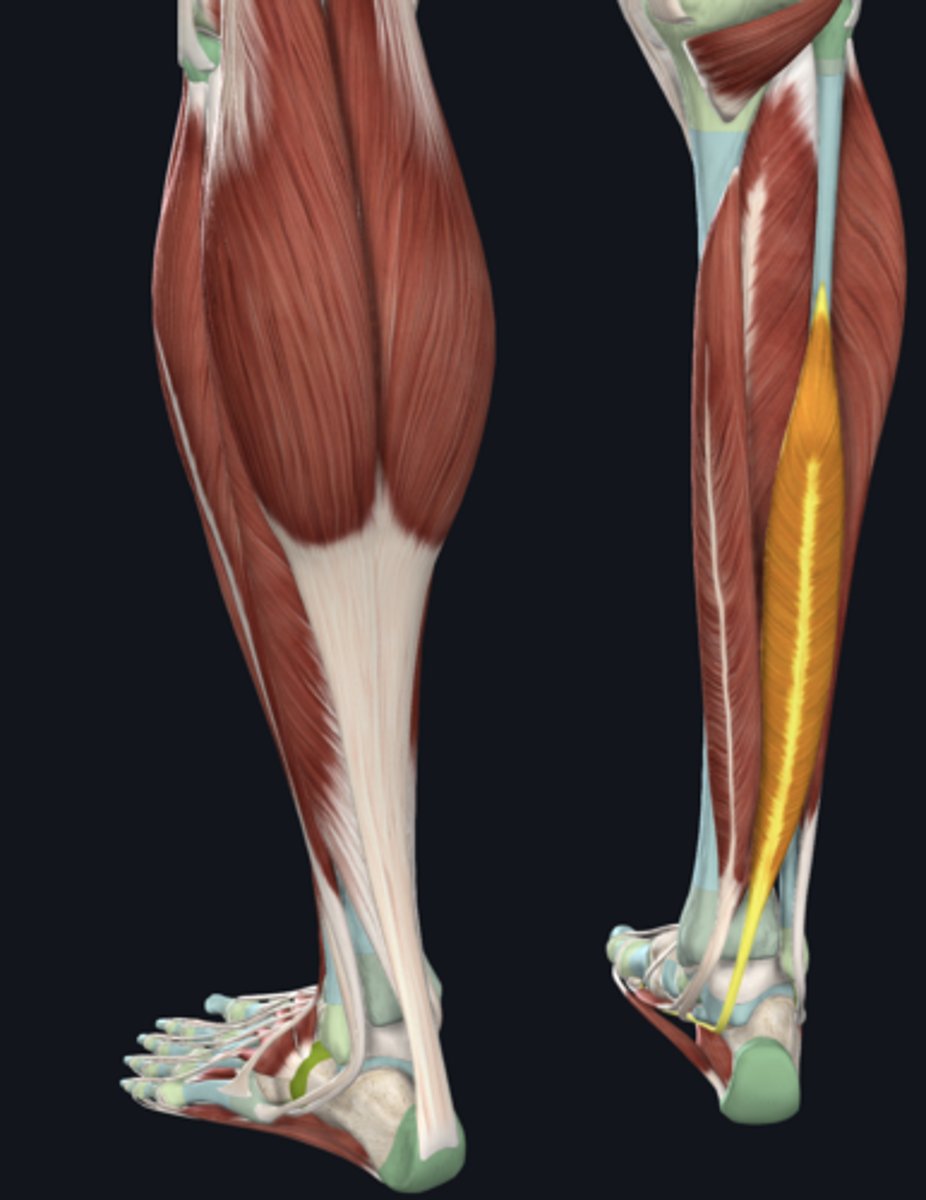

Medial head of gastrocnemius

Lateral head of gastrocnemius

Soleus

Plantaris